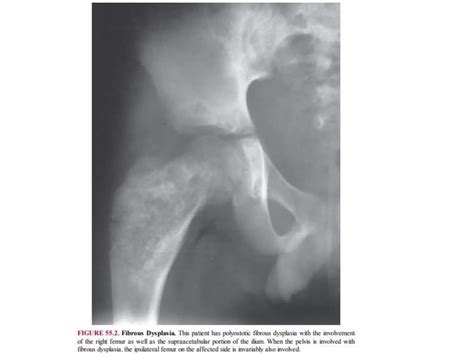

The discovery of Lytic Skeletal Lesions during a radiological examination often triggers a focused clinical investigation. These areas of bone destruction represent a wide spectrum of underlying pathologies, ranging from benign metabolic conditions to aggressive malignancies. Understanding the diagnostic approach, the biological mechanisms behind these lesions, and the clinical indicators is essential for healthcare providers and students of medicine alike. Because bone is a dynamic tissue constantly undergoing remodeling, the presence of lytic activity signifies an imbalance where bone resorption by osteoclasts outpaces bone formation by osteoblasts.

At its core, a lytic lesion is a focal area within the bone structure where mineral density has been significantly reduced. This reduction creates "holes" or voids in the bone, which are easily identified on X-rays as darker, radiolucent patches. The process is usually driven by the activation of osteoclasts—the cells responsible for breaking down bone tissue. When pathological processes, such as the invasion of metastatic cancer cells or inflammatory cytokines, trigger these cells, they erode the bone matrix prematurely.

The differential diagnosis for these lesions is vast, but clinicians often categorize them based on age, location, and the specific "look" of the lesion:

• Metastatic Carcinoma: Breast, lung, and renal cell carcinomas are common sources of bone metastases that appear lytic.